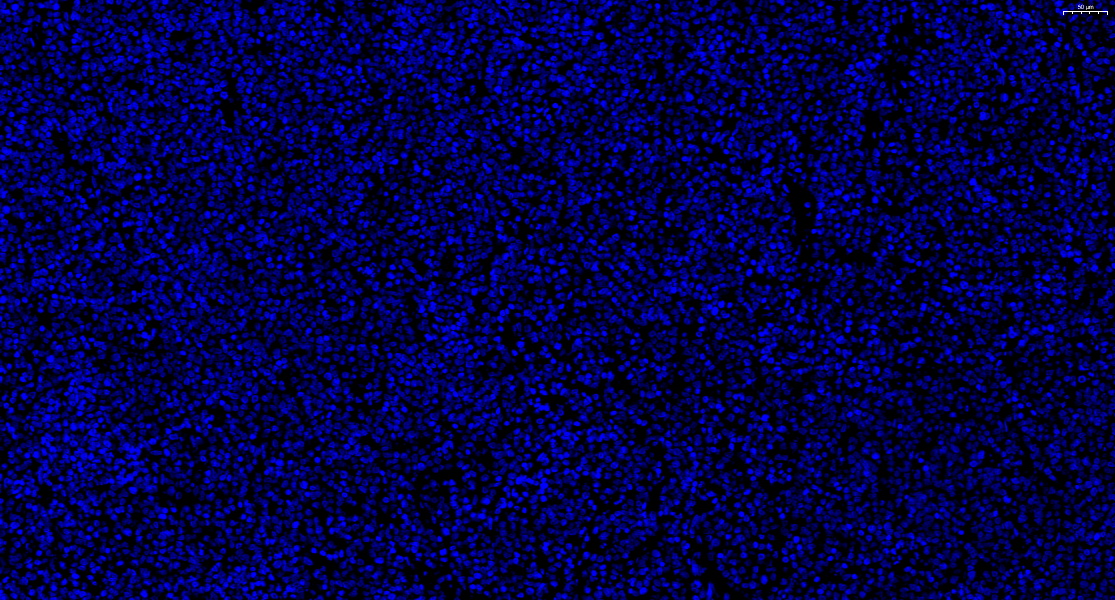

DAPI-淋巴瘤-20X